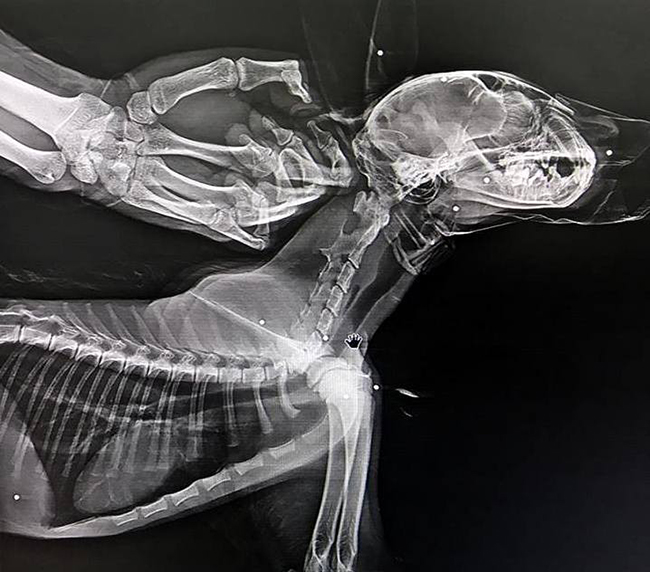

Vaşağın, Rehabilitasyon Merkezindeki muayenesinde çekilen röntgenlerde vücudunun çeşitli yerlerinde saçma taneleri bulunduğu tespit edildi. Gerekli tedavi ve rehabilitasyon işlemlerinin tamamlanmasının ardından vaşak, doğal ortamına bırakılacak.